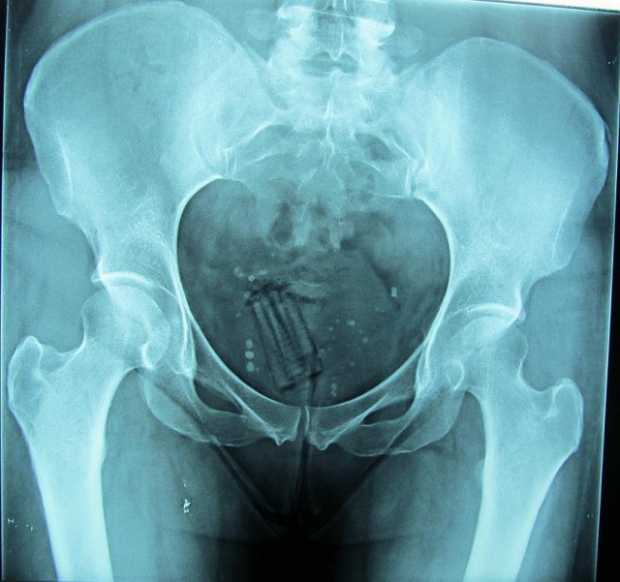

La visita que un hombre le hizo el sábado de la semana pasada a un amigo, interno en la cárcel La Blanca, de Manizales, le salió caro, pues intentó entrar droga en su ano y, de una vez, lo dejaron en el centro penitenciario.

El mayor Saúl Archila, director de La Blanca, manifestó que el hombre iba para el patio uno y que en los controles de entrada marcó positivo para marihuana y bazuco, con 228 y 50 gramos respectivamente, lo que le dio judicialización inmediata. El canino lo detectó.

Carlos Humberto Orozco Téllez, secretario de Salud de Manizales, indicó que la capa que cubre la vagina y el recto tiene una características de absorción tal, que en caso de que se rompa una bolsa con cocaína o heroína se podría generar una intoxicación severa.

"Con la marihuana no hay tanto riesgo, pero pueden generarse problemas en cualquier momento. La cocaína y la heroína están asociadas a la mortalidad alta en caso de ruptura de una bolsa plástica, convencional o preservativo. Ese rompimiento puede llevar hasta la muerte, pero más peligroso si se trata de heroína", explicó. En el caso del recto, se pueden ocasionar laceraciones, fisuras, infecciones y dificultad para defecar.